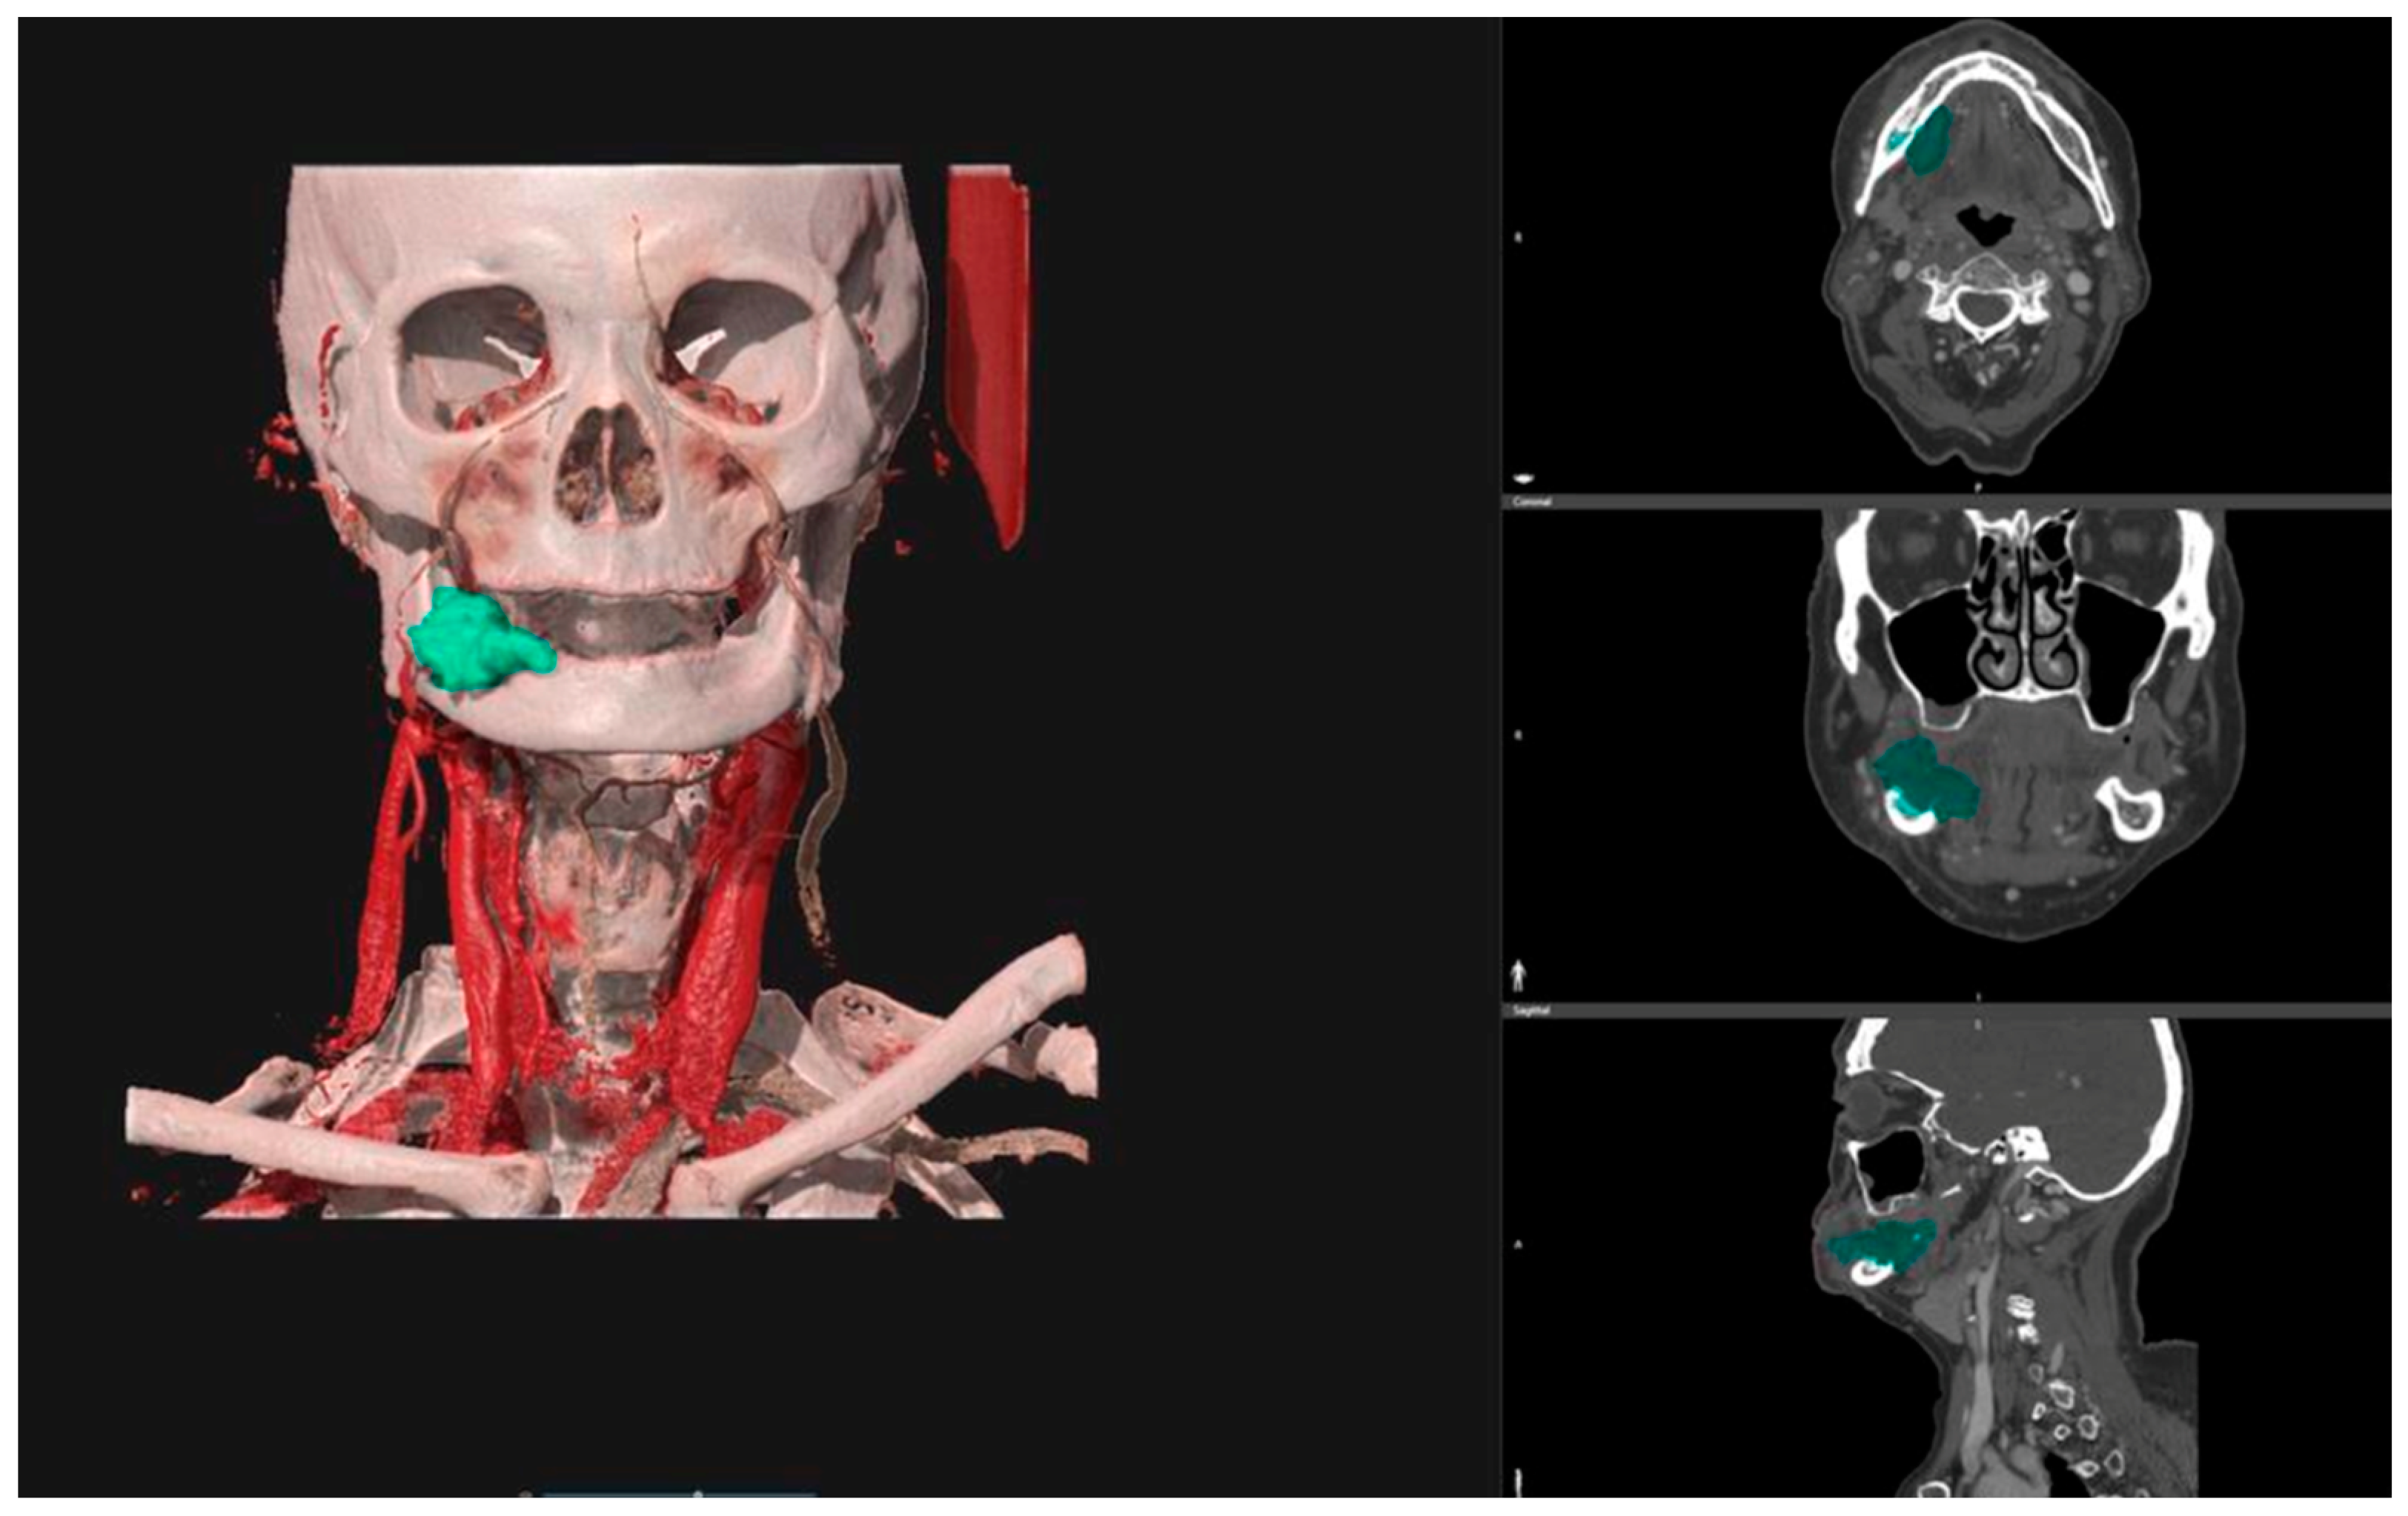

The pre-operative DICOM files obtained from CT scans were uploaded into the D2PTM software (3D Systems Inc., Rock Hill, SC, USA—software version n°1), a certified image segmentation software, which was used to obtain 3D digital models of the tumors via semi-automatic segmentation tools and free-hand segmentation refinements (Figure 1).

For each case, the segmented tumor was checked by the same radiologist specializing in head and neck oncology. The final tumor segmentation mask was converted into a 3D mesh and then exported in STL (Standard Triangulation Language) format. The corresponding tumor volume (Vt) was calculated for each 3D mesh.

Figure 1. D2PTM software interface shows the segmentation of a right alveolar mandibular tumor starting from a CT scan (coloured in green). On the right: the segmented region in the axial plane, in the coronal plane, and in the sagittal plane. On the left: the 3D reconstruction of the segmented tumor.